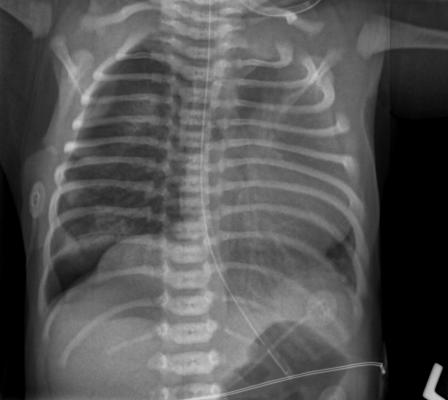

Researchers from Intermountain and Stanford studied the CheXpert system, an automated chest X-ray interpretation model developed at Stanford University that utilizes AI, to review X-ray images taken at a number of emergency departments at Intermountain hospitals throughout Utah.

The CheXpert model was developed by the Stanford Machine Learning Group, which used 188,000 chest imaging studies to create a model that can determine what is and is not pneumonia on an X-ray. These images were taken from the Stanford Medical Center in Palo Alto, Calif.

For the study, Intermountain radiologists categorized chest images from 461 Intermountain patients as being “likely,” “likely-uncertain,” “unlikely-uncertain” or “unlikely” to have pneumonia. They also identified images they believed showed pneumonia in multiple parts of the lungs, and whether these patients had parapneumonic effusion, which is fluid build-up between the lungs and chest cavity.